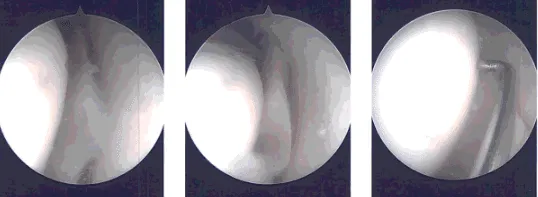

Intraoperative images

Time-out was called. Preoperative antibiotic was given. A lateral incision was given for the entry portal. Scope was entered. Patellofemoral compartment showed grade 1 to grade 2 osteoarthritic changes.

A medical entry portal was made using a spinal needle. Examination of the medial compartment showed a complex tear of the posterior horn of the medial meniscus. The tear was debrided. Medial meniscus was debrided with the use of straight biter, upbiter, and shaver.

Examination of the intercondylar notch showed intact ACL with degeneration. Examination of the lateral compartment showed medial frayed margins of the lateral meniscus which was debrided with the use of upbiter as well as the shaver.

The debridement of the patellofemoral joint was done and chondroplasty was performed with the use of the thermal wand and shaver. Suprapatellar plica was permanent which was removed with the use of a thermal wand.

The scope was entered from the medial portal and instruments were entered from the lateral portal to complete the medial meniscectomy.

Final pictures were taken and saved. The knee was thoroughly irrigated. The knee was drained. Closure was done with use of the # 3-0 nylon. A 9 cc of Naropin 0.5% mixed with 40 mg of Depo-Medrol was injected in the knee.